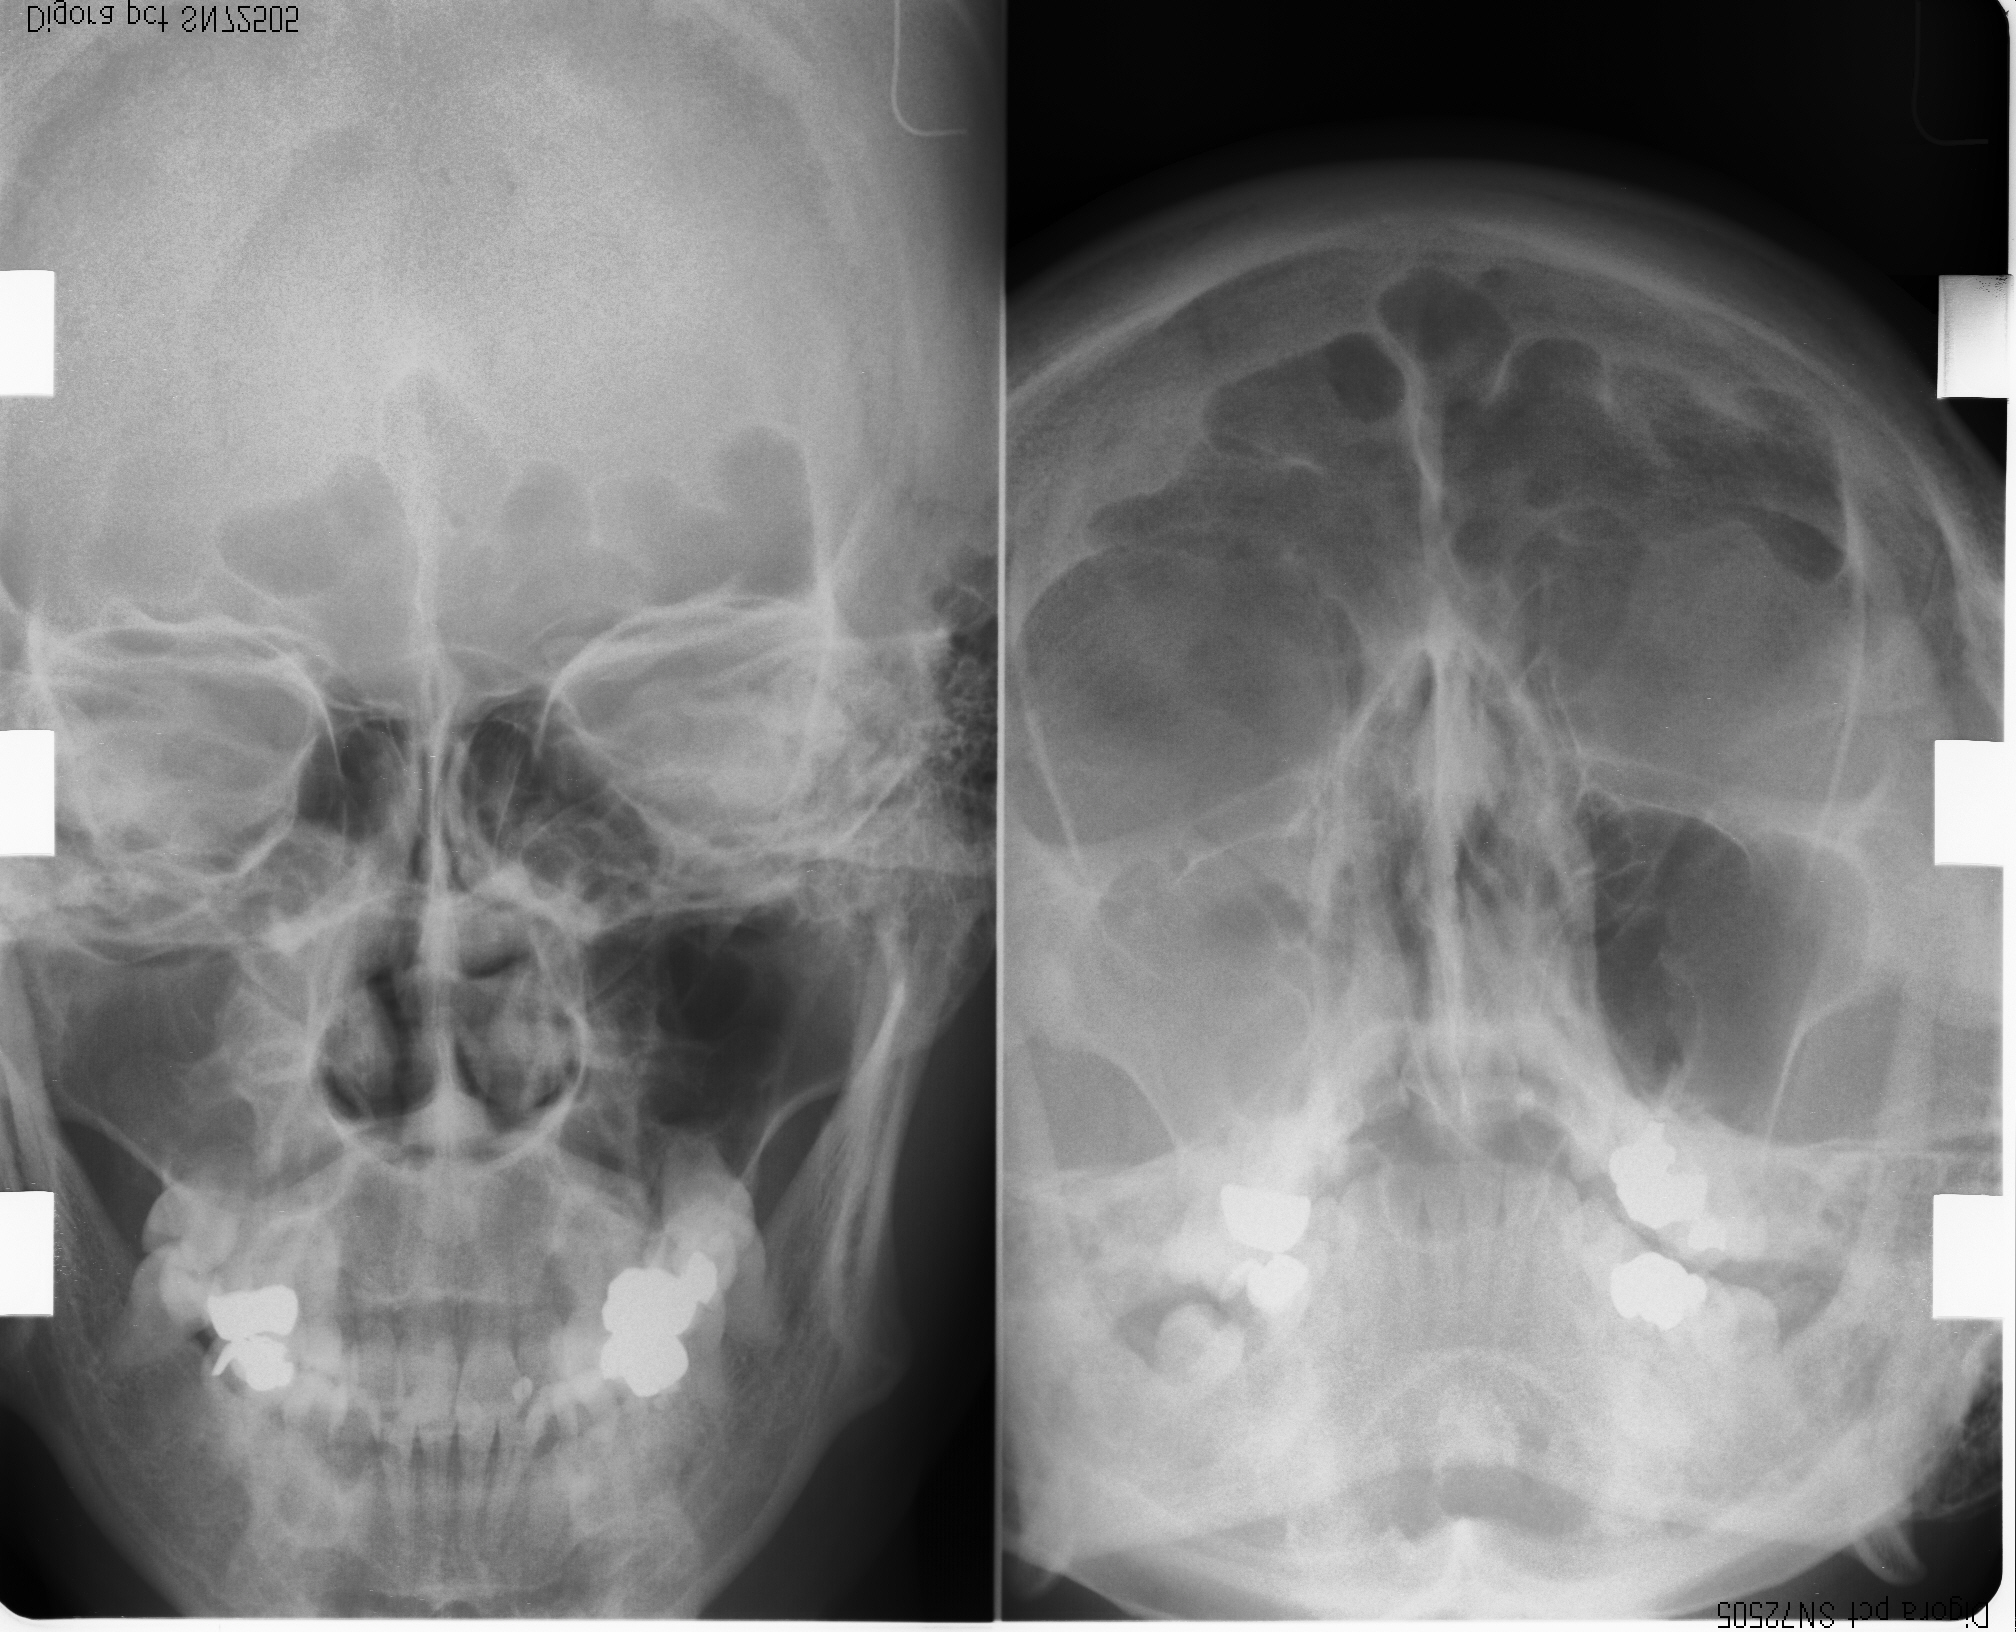

耳鼻科レントゲン・CR機器

当院のエックス線装置は少ない放射線量で撮影できます。デジタル画像読み取り(CR)装置との併用で、鮮明なデジタル画像がモニターに大きく映し出されます。